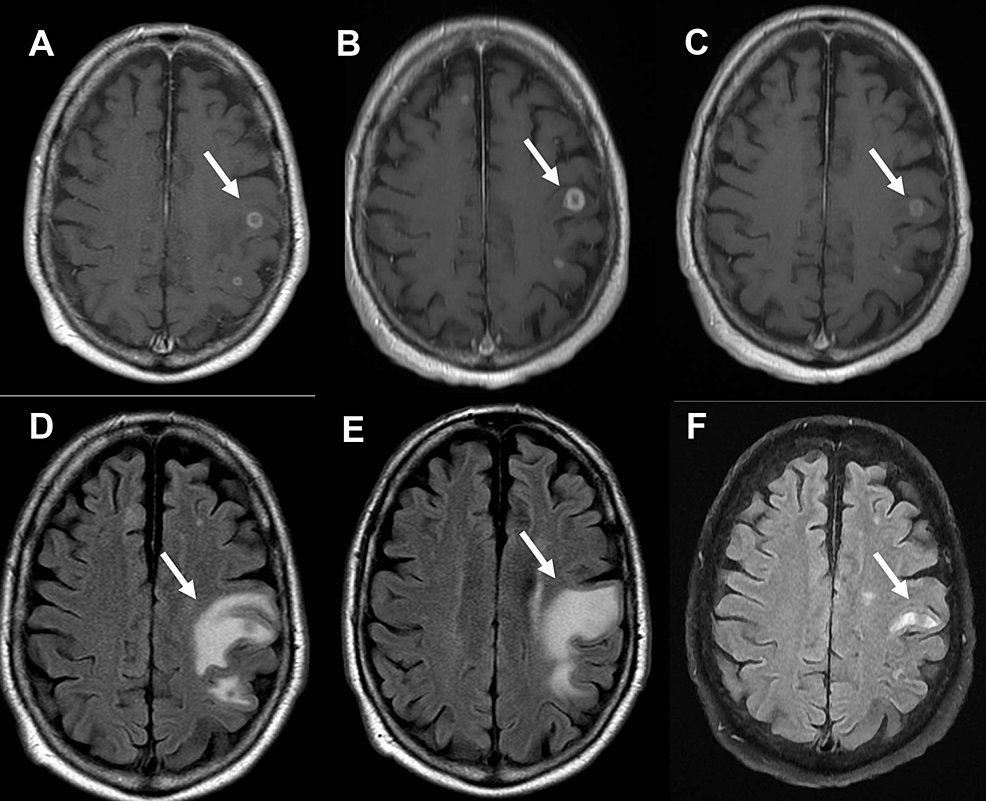

(PDF) Reactivation of Disseminated Histoplasmosis With Central Nervous Histoplasmosis Case Report Article A majority of patients were. Progressive disseminated histoplasmosis was the most frequent clinical. Diagnostic of histoplasmosis was confirmed by histology and pcr analysis on biopsy. To our knowledge, this is the first. Disseminated histoplasmosis is usually associated with immunosuppressive conditions like aids. 17.7% of the cases were attributed to h. The most frequently identified species was histoplasma capsulatum (79/113 cases,. Histoplasmosis Case Report Article.

(PDF) Histoplasmosis appearing as multiple mass lesions of the brain Histoplasmosis Case Report Article Progressive disseminated histoplasmosis was the most frequent clinical. To our knowledge, this is the first. Diagnostic of histoplasmosis was confirmed by histology and pcr analysis on biopsy. 17.7% of the cases were attributed to h. The most frequently identified species was histoplasma capsulatum (79/113 cases, 69.9%); Disseminated histoplasmosis is usually associated with immunosuppressive conditions like aids. A majority of patients. Histoplasmosis Case Report Article.